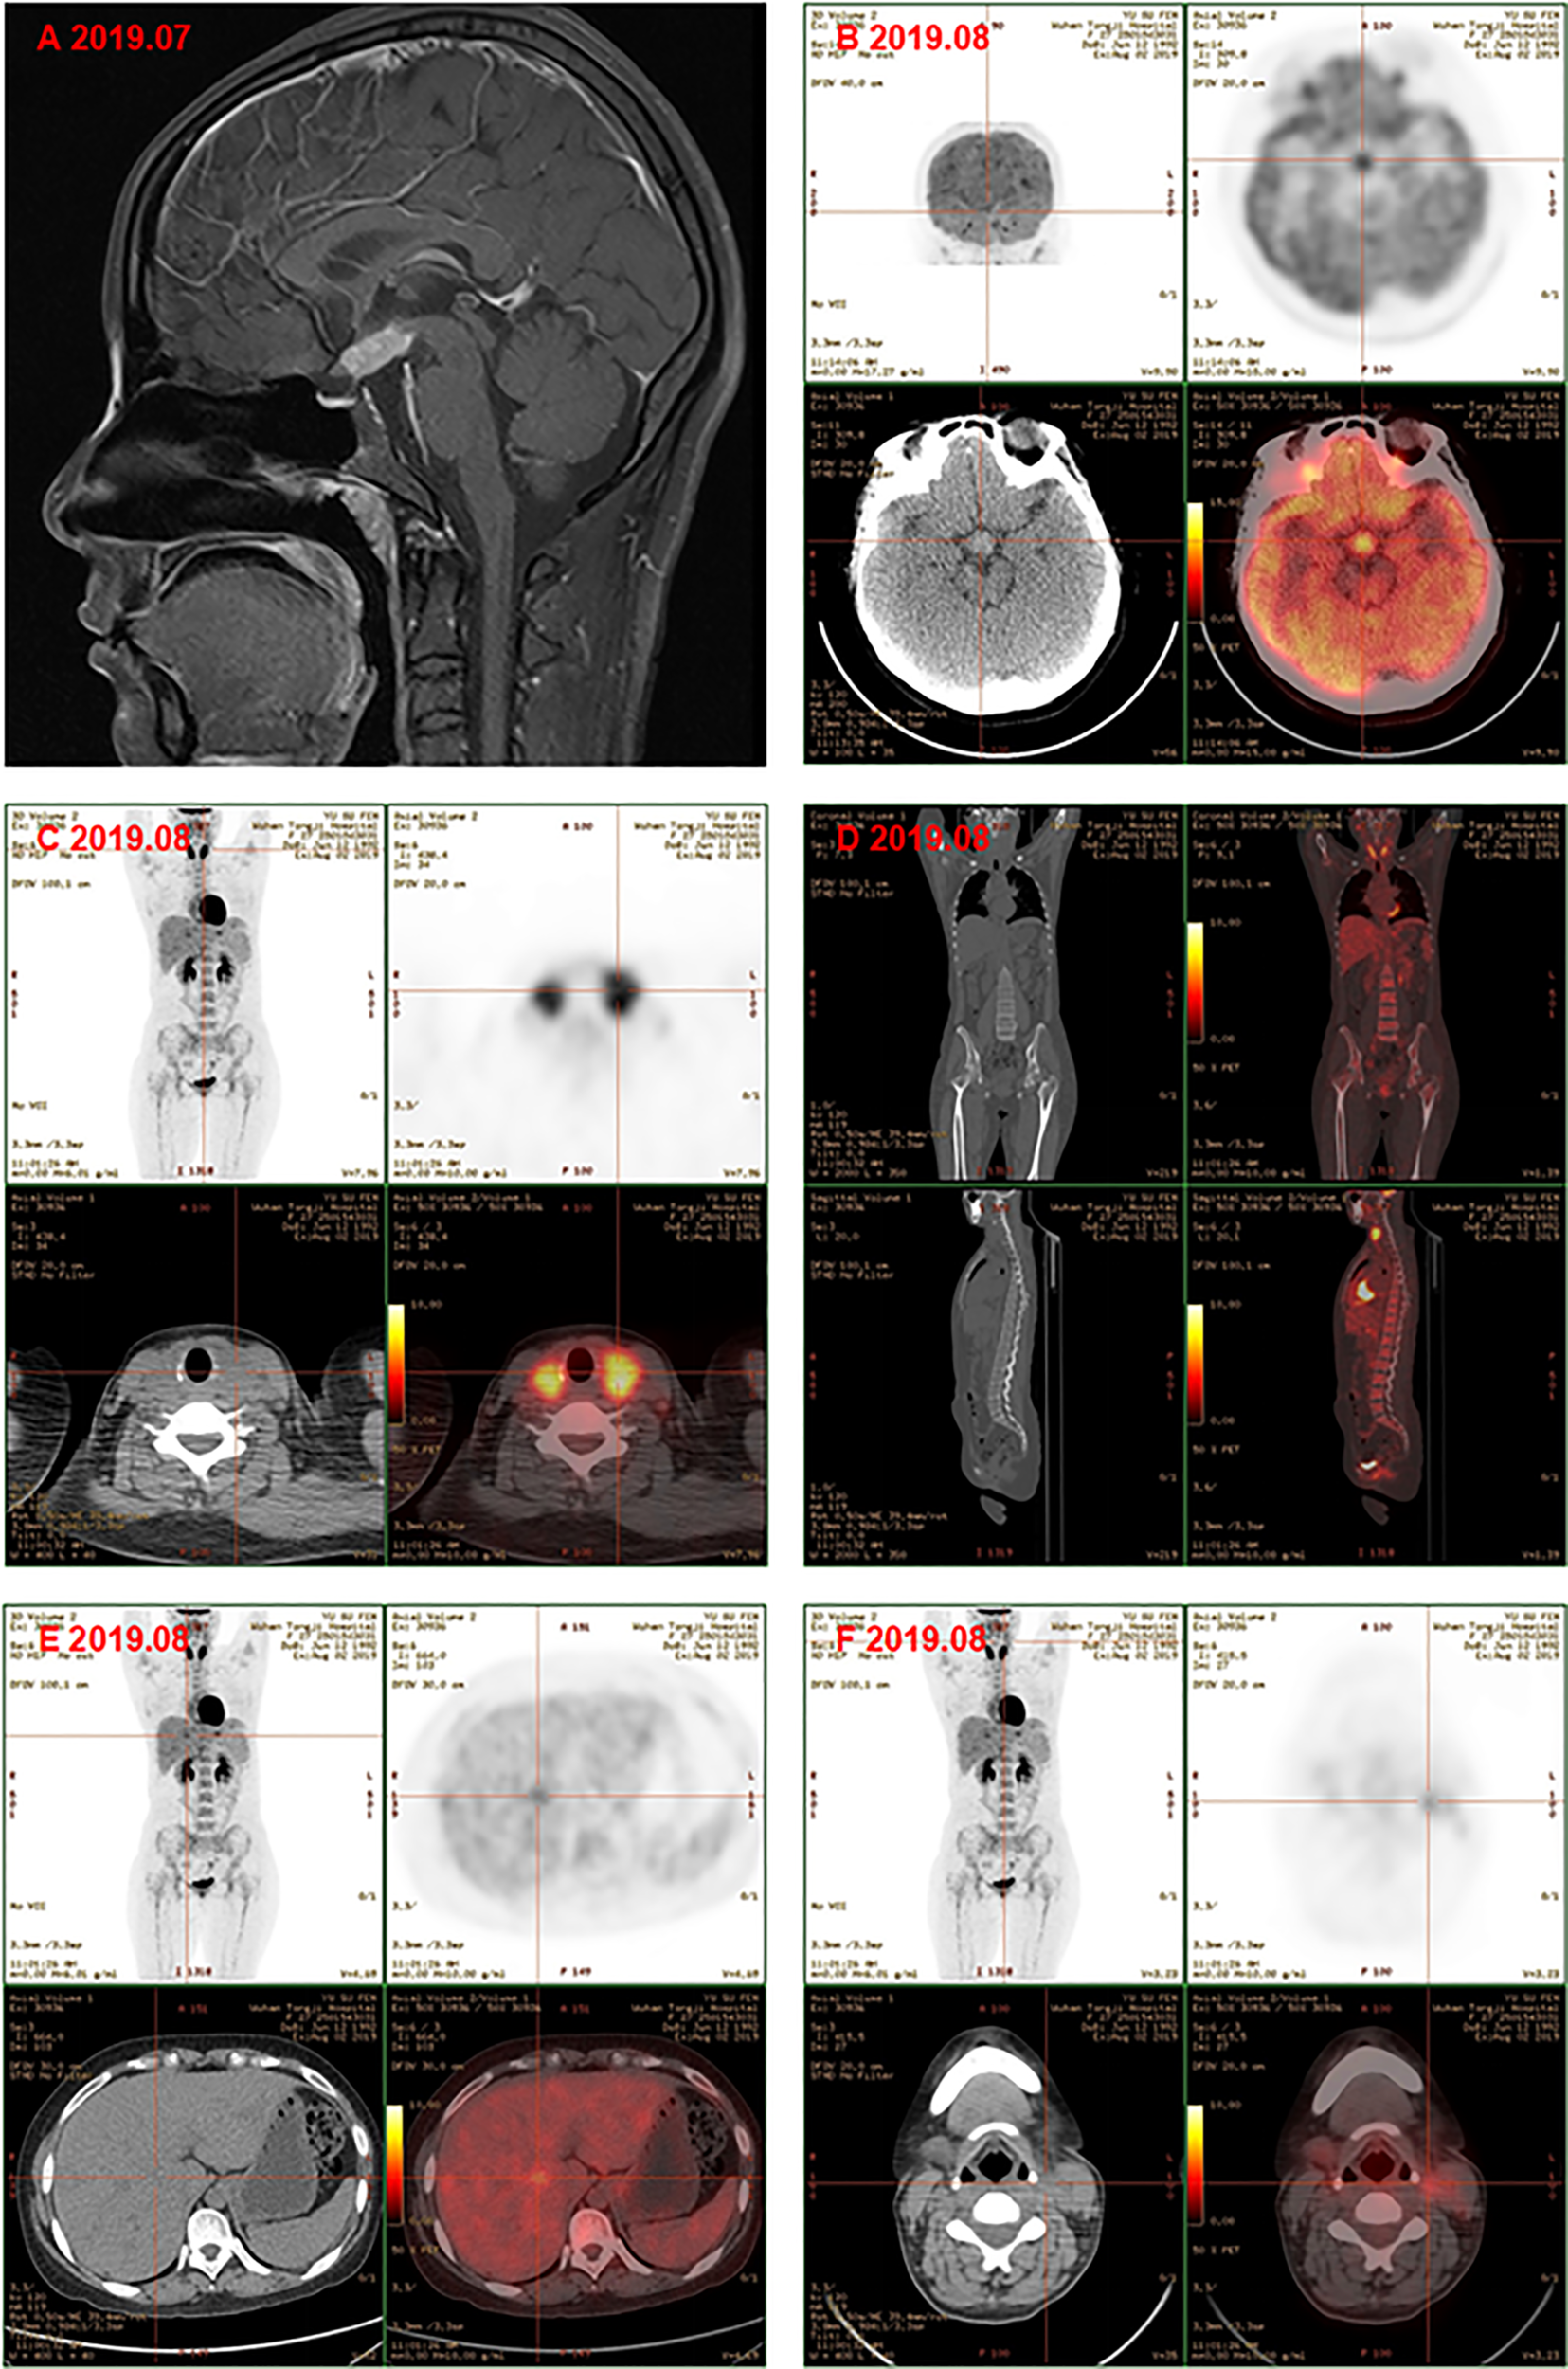

Subsequently, color doppler ultrasound of the thyroid and lymph nodes revealed a diffuse heterogeneous thyroid enlargement with slightly rich blood flow and multiple enlarged lymph nodes on both sides of the neck. To further clarify the goiter, the patient underwent a thyroid and lymph node biopsy. The results suggested an epithelial neoplasm, with heavy eosinophilic infiltration (Figures 1A–C), for which immunohistochemistry showed that the Langerhans cells expressed CD207 (langerin) (Figure 1D), S-100 (Figure 1E), CD1a (Figure 1F), and Ki67 (Figure 1G), but were negative for IgG4 (Figure 1H) and IgG (Figure 1I). MRI of the pituitary suggested nodular thickening and enhancement of the hypothalamus (Figure 2A). Under the supervision of a specialist in hematology, tumor metabolic imaging (PET/CT) was performed, and the results were as follows: 1. Nodular thickening of hypothalamus and increased metabolism (Figure 2B); 2. The volume of bilobed thyroid increased and metabolism increased (Figure 2C); 3. Multiple lymph nodes increased (bilateral neck, mediastinum paratracheal, hilar region, portal space, retroperitoneum, bilateral iliac vascular), increased metabolism (Figure 2D); 4. Multiple slightly low density shadows in the liver, increased uneven metabolism (Figure 2E); 5. Bilateral tonsil metabolism increased, and bone marrow metabolism uneven slightly increased (Figure 2F).

Figure 2

(A) Magnetic resonance image of pituitary gland showd the nodular thickening and enhancement of the hyphothalamus, and the pituitary itself became thinner. PET-CT showed the metabolism of hypothalamus was higher (B); the volume of bilobe thyroid and metabolism increased (C); multiple lymph nodes icreased and metabolism increased, bone marrow metabolism slightly increased (D); multiple slightly low density shadows in the liver (E); bilateral tonsil metabolism increased (F) before chemotherapy.

Finally, the clinical picture and the biopsy findings were consistent with a diagnosis of MS-LCH with pituitary, thyroid, lymph node, and liver involvement. The patient was then given DVP chemotherapy (vinblastine 4mg day1, cyclophosphamide 600mg day1, prednisone 10mg days1-5). In addition, hormone replacement therapy and antidepressant therapy were continued. After three cycles, favorable evolution was noted, with a good tolerance of treatment and a clear relief of results of PET/CT examination. Comparison with previous PET/CT (Figures 2B–F): 1. Hypothalamic nodule was thickened, and slightly larger than before; the metabolism of hypothalamus was higher (Figure 3A); 2. The volume and metabolism of thyroid gland decreased (Figure 3B); 3. The range of primary lesions (neck, mediastinum, and abdominal lymph nodes) was significantly reduced, and the metabolism was significantly reduced/subsided (Figure 3C); 4. Metabolism of the multiple foci in the liver subsided (Figure 3D); 5. The metabolism of bilateral tonsils and bone marrow was increased, which was similar to the previous (Figure 3C). Given this, we upped the dose of DVP (vinblastine 4mg day1, cyclophosphamide 1000mg day1, prednisone 10mg days (1-5) in the fourth chemotherapy cycle.